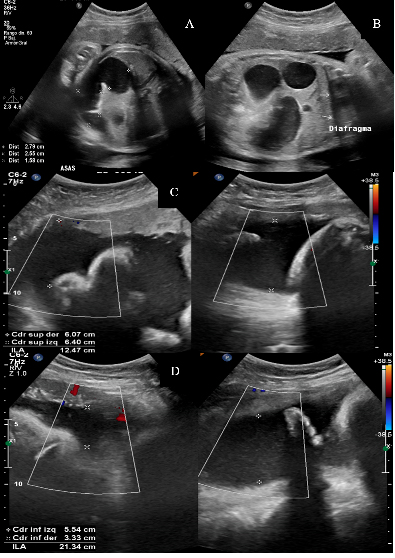

Síndrome de bandas amnióticas: reporte de caso y revisión de literatura

Yolima Alfaro, Luis Fernando Rodríguez, María Mercedes Domínguez, Luis Fernando Molineros Gallón, Ana Ximena Pintae, José Dario Portillo-Miño

14-17